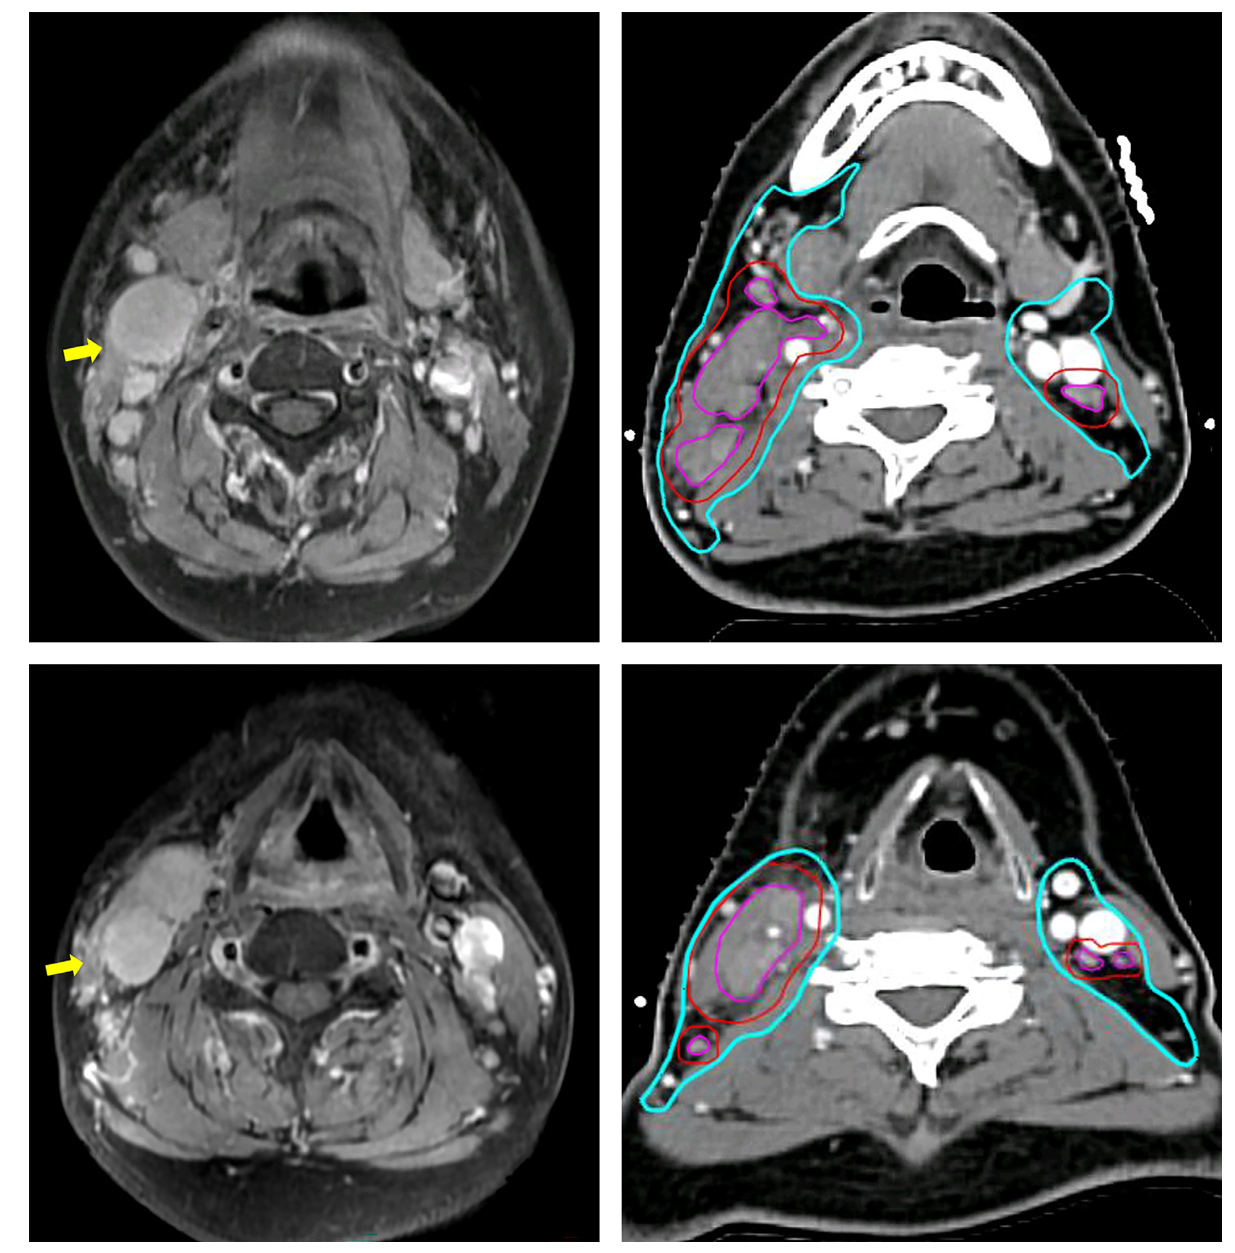

在淋巴结临床靶区的勾画上同样体现了精准化的理念,对于无淋巴结外侵犯的淋巴结其高剂量靶区外扩范围也建议为零至五毫米而对于伴有晚期淋巴结外侵犯者则建议五至十毫米外扩,对于可疑但未明确的淋巴结建议不进行外扩仅给予60 Gy剂量,对于低风险淋巴结靶区新指南推荐不再采用固定的外扩模式而是覆盖相应的淋巴结引流区并给予50 Gy剂量,在淋巴结引流区的选择性覆盖上新指南建议对于Level IV和Vb-c区仅在同侧Level III或Va区受累时才需覆盖否则可以省略,这体现了对淋巴结逐级引流规律的遵循,同时新指南明确了Level Ib区覆盖的适应症包括Ib区淋巴结受累、颌下腺受累或其第一站引流区域受累但对于颌下腺本身若未受累则可从其覆盖范围内剔除,在解剖边界方面新指南特别将Level IVa区的前界从胸锁乳突肌前缘修改为舌骨下带状肌群的后缘以减少对甲状腺的照射剂量,并将Level II区的上界延伸至颅底以确保对咽后淋巴结和茎突后区的充分覆盖,对于下界则根据受累水平的不同进行差异化规定若Level IV或Vb-c受累则下界应延伸至锁骨头上缘并确保在受累淋巴结下方有两厘米的边缘。

图2 淋巴结临床靶区勾画示意图